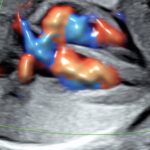

Ofrecemos servicios de ecografía obstétrica avanzada (genética, estructural, Doppler) y seguimiento experto de embarazos de alto riesgo, utilizando tecnología de punta para diagnósticos precisos